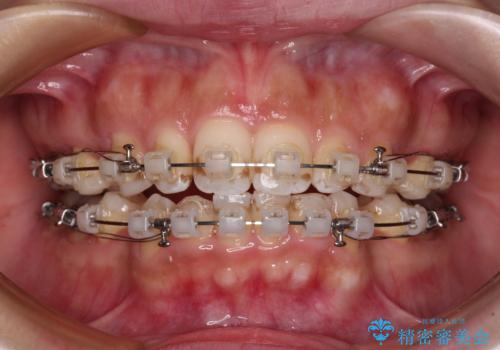

唇が閉じにくい ワイヤー装置での抜歯矯正

- 矯正装置

- クリアブラケット

- 治療期間

- 1年11ヶ月

上下ともに前歯が少し舌側に傾斜したような仕上がりとなりましたが、口が閉じやすくなったとのことで、患者様には大変満足していただけました。